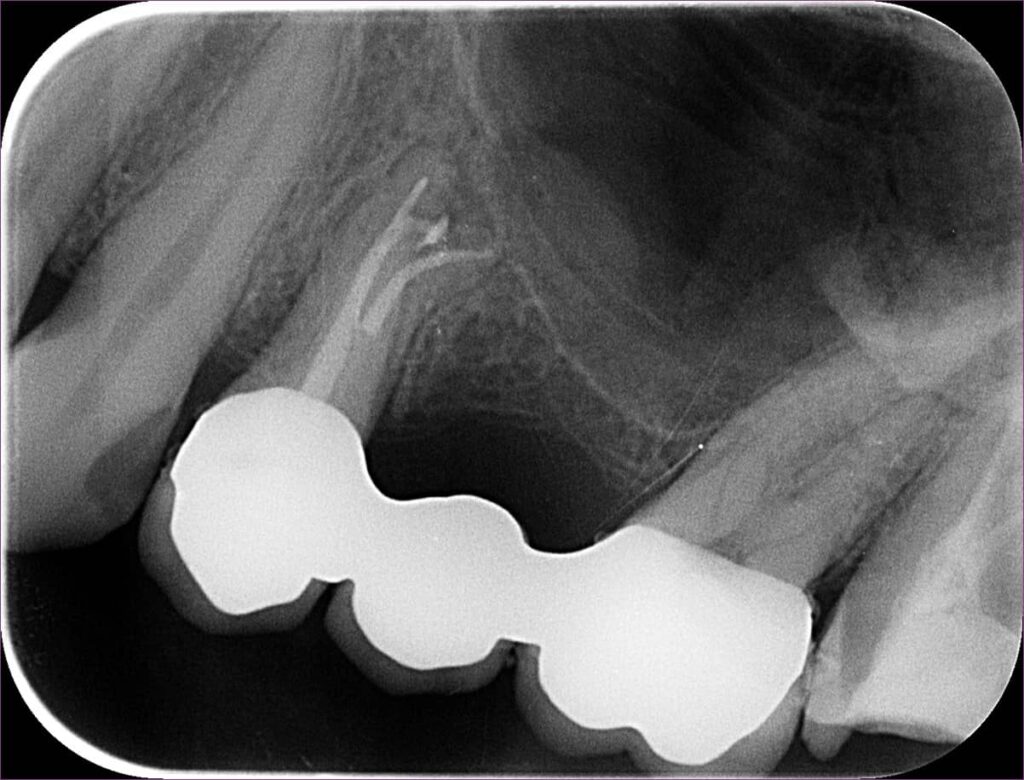

Ezen a képen látható a fog kontrollfelvétele. A gyökértömést követően a fogat üvegszálas-csapos megerősítéssel láttuk el, ezt követően pedig a kezelőorvos beragasztotta az elkészült hídpótlást.